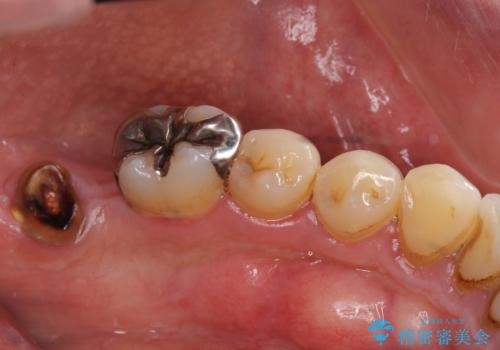

インプラント治療・セラミック治療を含む 全顎的虫歯治療

- 「 仕事が忙しく、虫歯を放置しすぎてしまった。この際全てきっちりと治したい。」と来院されました。

・歯の欠損

・虫歯

・深い虫歯

・欠損の放置による対合歯の挺出

・咬合平面の乱れ

・感染根管

以上のような問題を、徹底的な虫歯治療、歯周外科、インプラント治療、部分矯正治療、精密根管治療を用いてひとつずつ解決ししっかりと長期的に食事を楽しめるような口腔内環境の再構築を目指します。